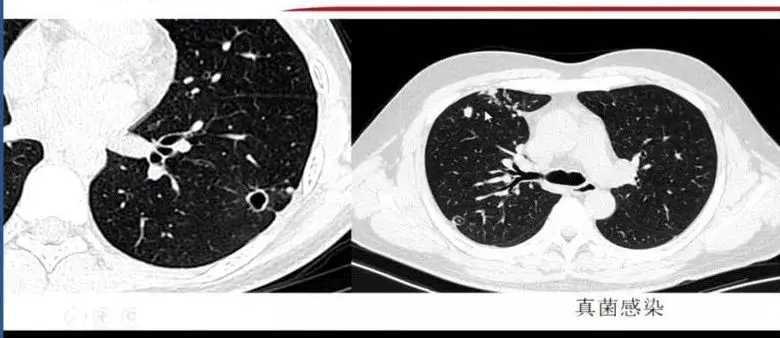

10. 真菌

真菌不同时期表现不同,有晕征 、支气管充气征、新月征、胸膜牵拉等可能表现。

隐球菌作为常见的真菌感染,易误诊为肺癌,影像表现为胸膜下带有晕征的小结节,三维重建后呈球形,单个结节诊断较为困难。隐球菌出现空洞时,空洞位于中央,可存在分隔,诊断时需要参考实验室检查结果。

图13 隐球菌